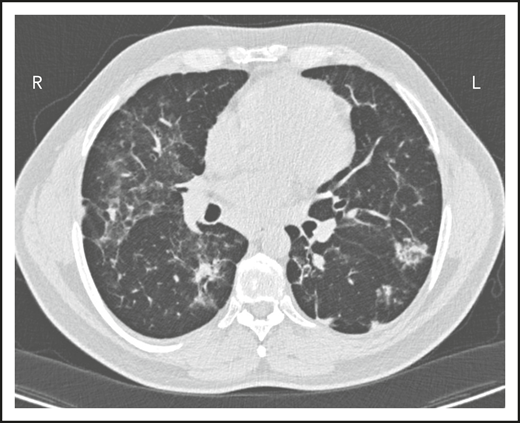

A second common reason for a patient to come to the attention of hematologists is the finding of an enlarged spleen, especially in an adult with lymphadenopathy. This was the reason in patient 2, who is now a 46-year-old male professional dog walker. At the age of 31, he was found to have an enlarged spleen together with cervical and axillary lymphadenopathy. Hematology was consulted, and the lymph node was biopsied; pathology revealed that he had noncaseating granuloma. He was then referred to pulmonology and, with this evidence, was diagnosed with sarcoidosis and treated with steroids for some months, but he stopped the treatment. Although he had no obvious respiratory symptoms over the following 15 years, he had a slow decline in lung function, and chest computed tomography showed hilar lymphadenopathy, ground-glass opacities with nodules, and bronchiectatic changes (Figure 2). In 2018, he had acute bacterial pneumonia, became concerned, and found on the internet that granulomata in the lungs and an enlarged spleen might be related to low serum immunoglobulin levels. He asked that this be tested; when this test was performed, he had striking low serum immunoglobulins: IgG, 97 mg/dL; IgA, <5 mg/dL; IgM, 27 mg/dL. However, within the month, he was hospitalized for pneumonia due to metapneumovirus. The diagnosis of CVID was finally made, and immunoglobulin treatment was started. The patient’s spleen remains large.

The patient in clinical case 2 had a slow decline in lung function due to his immune defect, but this was assumed to be due to sarcoidosis. Chest computed tomography showed ground-glass opacities with numerous nodules, hilar lymphadenopathy, and bronchiectatic changes. With granuloma on biopsy, these changes were consistent with granulomatous lymphocytic interstitial lung disease.